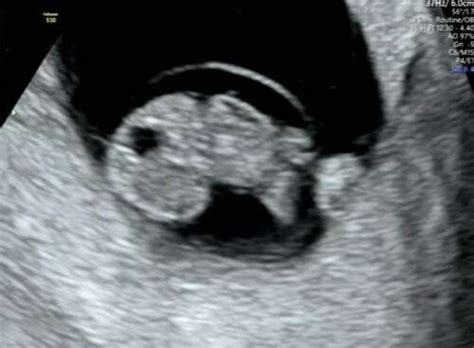

8 weken zwanger De eerste echo!

Een vroege echo rond 7-8 weken zwangerschap, kijkt de echoscopist of het bevruchte eitje zich op de juiste plek in de baarmoeder heeft ingenesteld (niet buitenbaarmoederlijk) en of het hartje klopt Nog meer zie je op playlist 8 weken zwanger, 8 weken zwanger en 8 weken echo

Hebben jullie bij de echo rond 8-9 weken een kloppend hartje gezien, dan is die kans al veel kleiner en eind nog maar 2 tot 3 van de 100 zwangerschappen in een miskraam . Hebben jullie bij de echo rond 8-9 weken een kloppend hartje gezien, dan is die kans al veel kleiner en eind nog maar 2 tot 3 van de 100 zwangerschappen in een miskraam. Wat zien ze bij 8 weken echo? 8 weken zwanger: vitaliteitsecho We vertelden al dat je rond de 8 weken zwangerschap de eerste echo krijgt, deze echo wordt ook wel de vitaliteitsecho genoemd

Ultrasone Klank Van Een Foetus Bij 8 Weken 1 Dag Stock Foto Image of ultrageluid, prenataal. Hoe ziet foetus van 8 weken eruit? Na 8 weken spreken we van foetus omdat alle organen in beginsel aanwezig zijn. Daarna kijken we of er sprake is van een meerling.